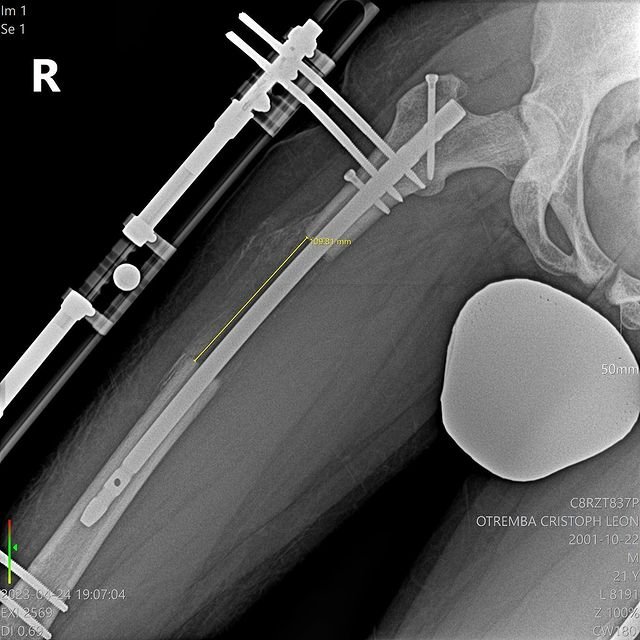

@le_tremba表示,因為他的原生身高只有172.5公分,讓他覺得自己偏矮、時常感到自卑,「老實說,170公分算滿矮的,這影響了我的自信心,我總覺得這樣不夠Man,因為就連有些女生都長到175公分甚至更高了。」因此他一心想要解決這個困擾他已久的身高問題,後來他特地飛到土耳其進行增高手術,前後共手術了3次,讓他的身高增加了10.5公分、來到183公分!

不過增高手術也不是那麼容易的,必須使腿部骨骼斷裂、並打入增長骨釘促進骨骼延長,不但程序繁複,接受手術者也必須承受很大的風險以及可能會發生的併發症,而且也不是做完手術就立刻長高,還需要一段恢復期來讓骨頭、肌肉、皮膚和神經慢慢伸展開來,過程當然也是必須忍受這非比尋常的「生長痛」;但@le_tremba堅信這個決定是正確的,他甘之如飴。